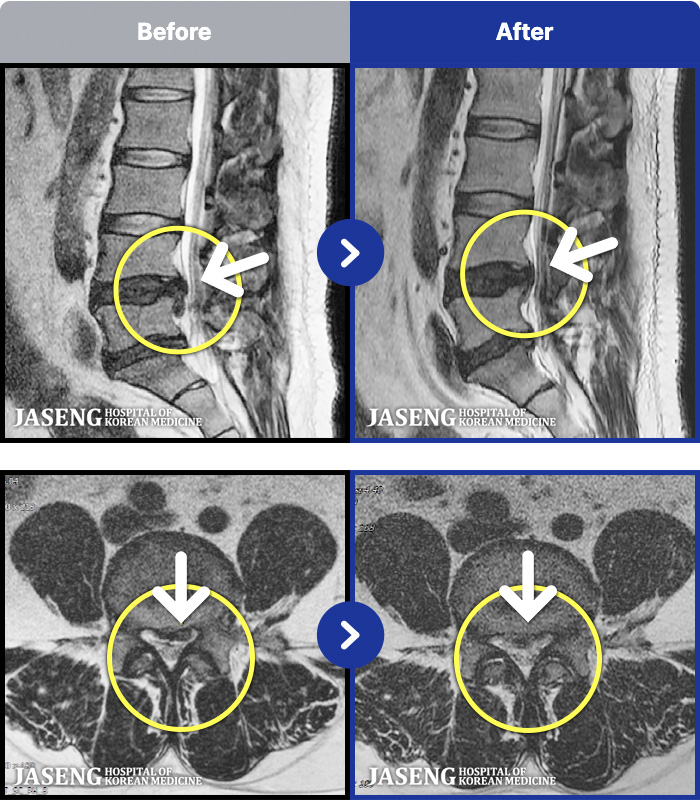

[뱸] 19.11.28~25.05.06